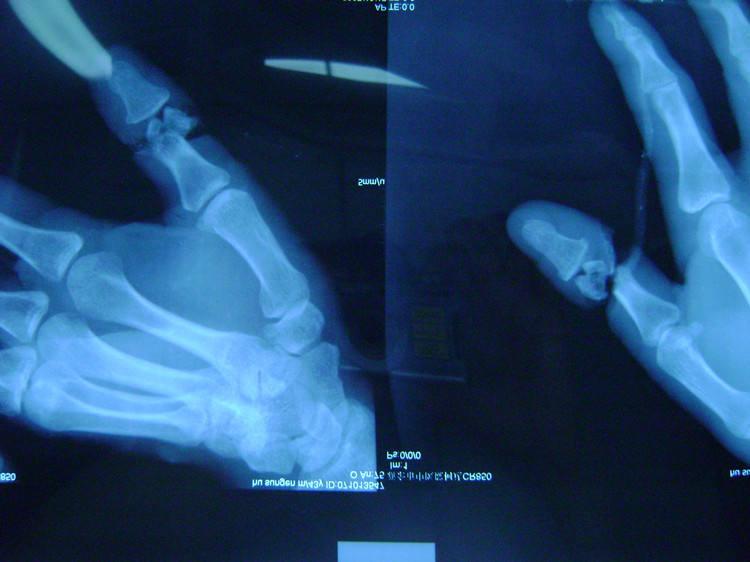

拇指撕脱性离断再植手术

拇指断指再植